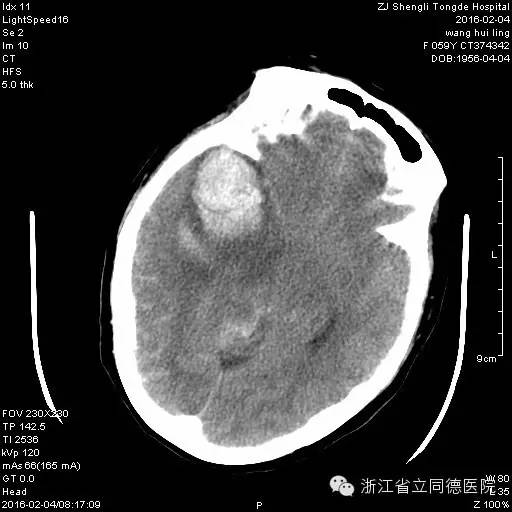

虽然名字里有个“瘤”字,但脑动脉瘤并不是真正的肿瘤,而是指脑动脉血管壁局部变薄,由于高速血流持续冲击,形成与血管相连通的囊性扩张。

颅内动脉瘤结构示意图展示血管异常扩张部位

它就像一颗“不定时炸弹”

一旦破裂,致死率极高。据统计,约有三分之一的患者在入院前就已经死亡,剩下的三分之二也有再次出血的风险。